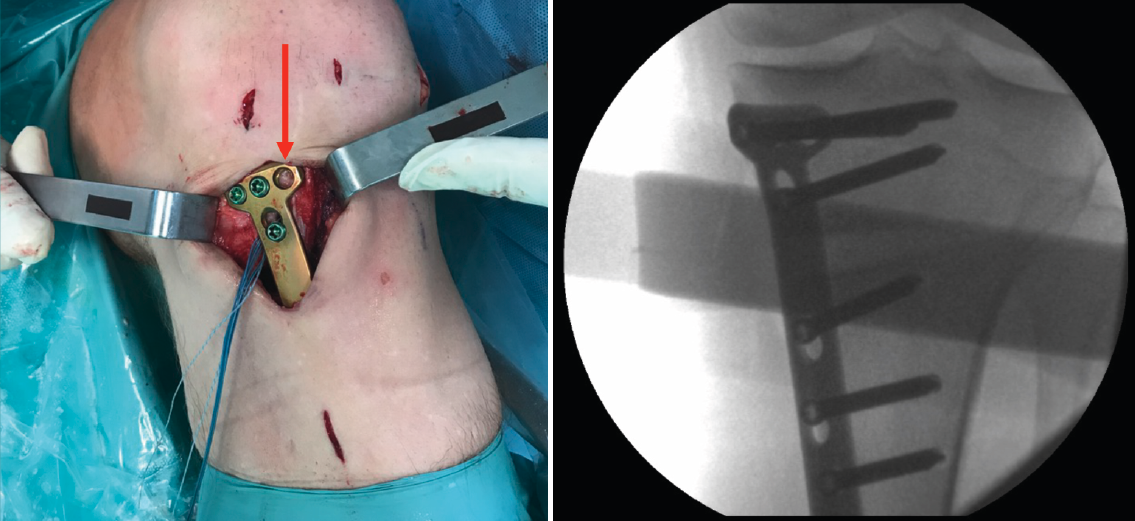

Una vez hecho el túnel tibial, se introduce la plastia y se fija a nivel femoral y tibial (Figura 7). Si se utiliza una plastia de isquiotibiales, los autores recomiendan una fijación femoral cortical de suspensión regulable, dejando unos milímetros para el ajuste final después de la colocación de la placa de osteotomía. Una vez fijada la plastia, se procede a la colocación de la placa de osteotomía TomoFix® (Synthes, Oberdorf, Switzerland) para la tibia proximal medial (Figura 8). En la mayoría de los casos el tornillo más anterior coincide con el túnel tibial de RLCA, motivo por cual no se coloca (Figura 9).

Figura 9. Fijación de la placa con tornillos. Se señala con la flecha la ausencia del tornillo más anterior, dada su coincidencia con el túnel tibial.